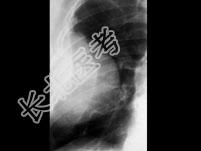

多项选择题以下描述符合周围型肺癌的X线表现为 ( )

A、较大肿块中心部分坏死液化

B、大肿块内壁不平

C、块影边缘模糊毛糙

D、多有明显液平面

E、肺野周围弥漫性圆形块影